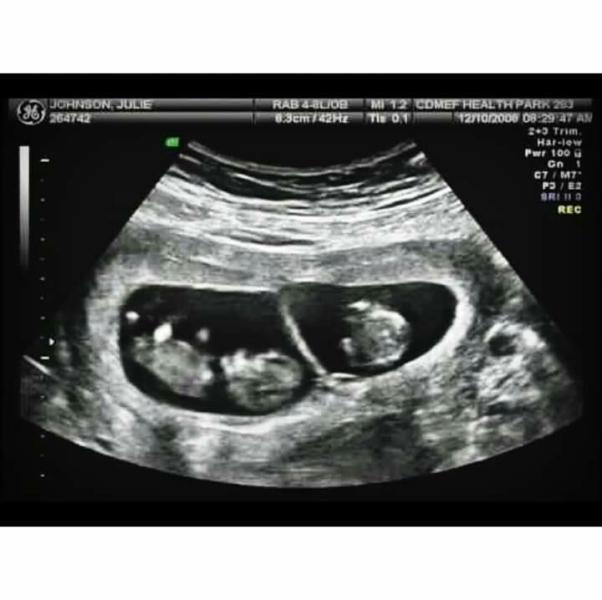

Когда я увидела вот это фото, меня словно током ударило!

Эти два маленьких человечка, которым уже 5 недель и я смотрю на них и улыбаюсь 😊

Особенно, от того,что их там двое😊😊

Я даже не знаю, мальчики или девочки, а может мальчик и девочка👼👼

Сразу два малыша!!!....